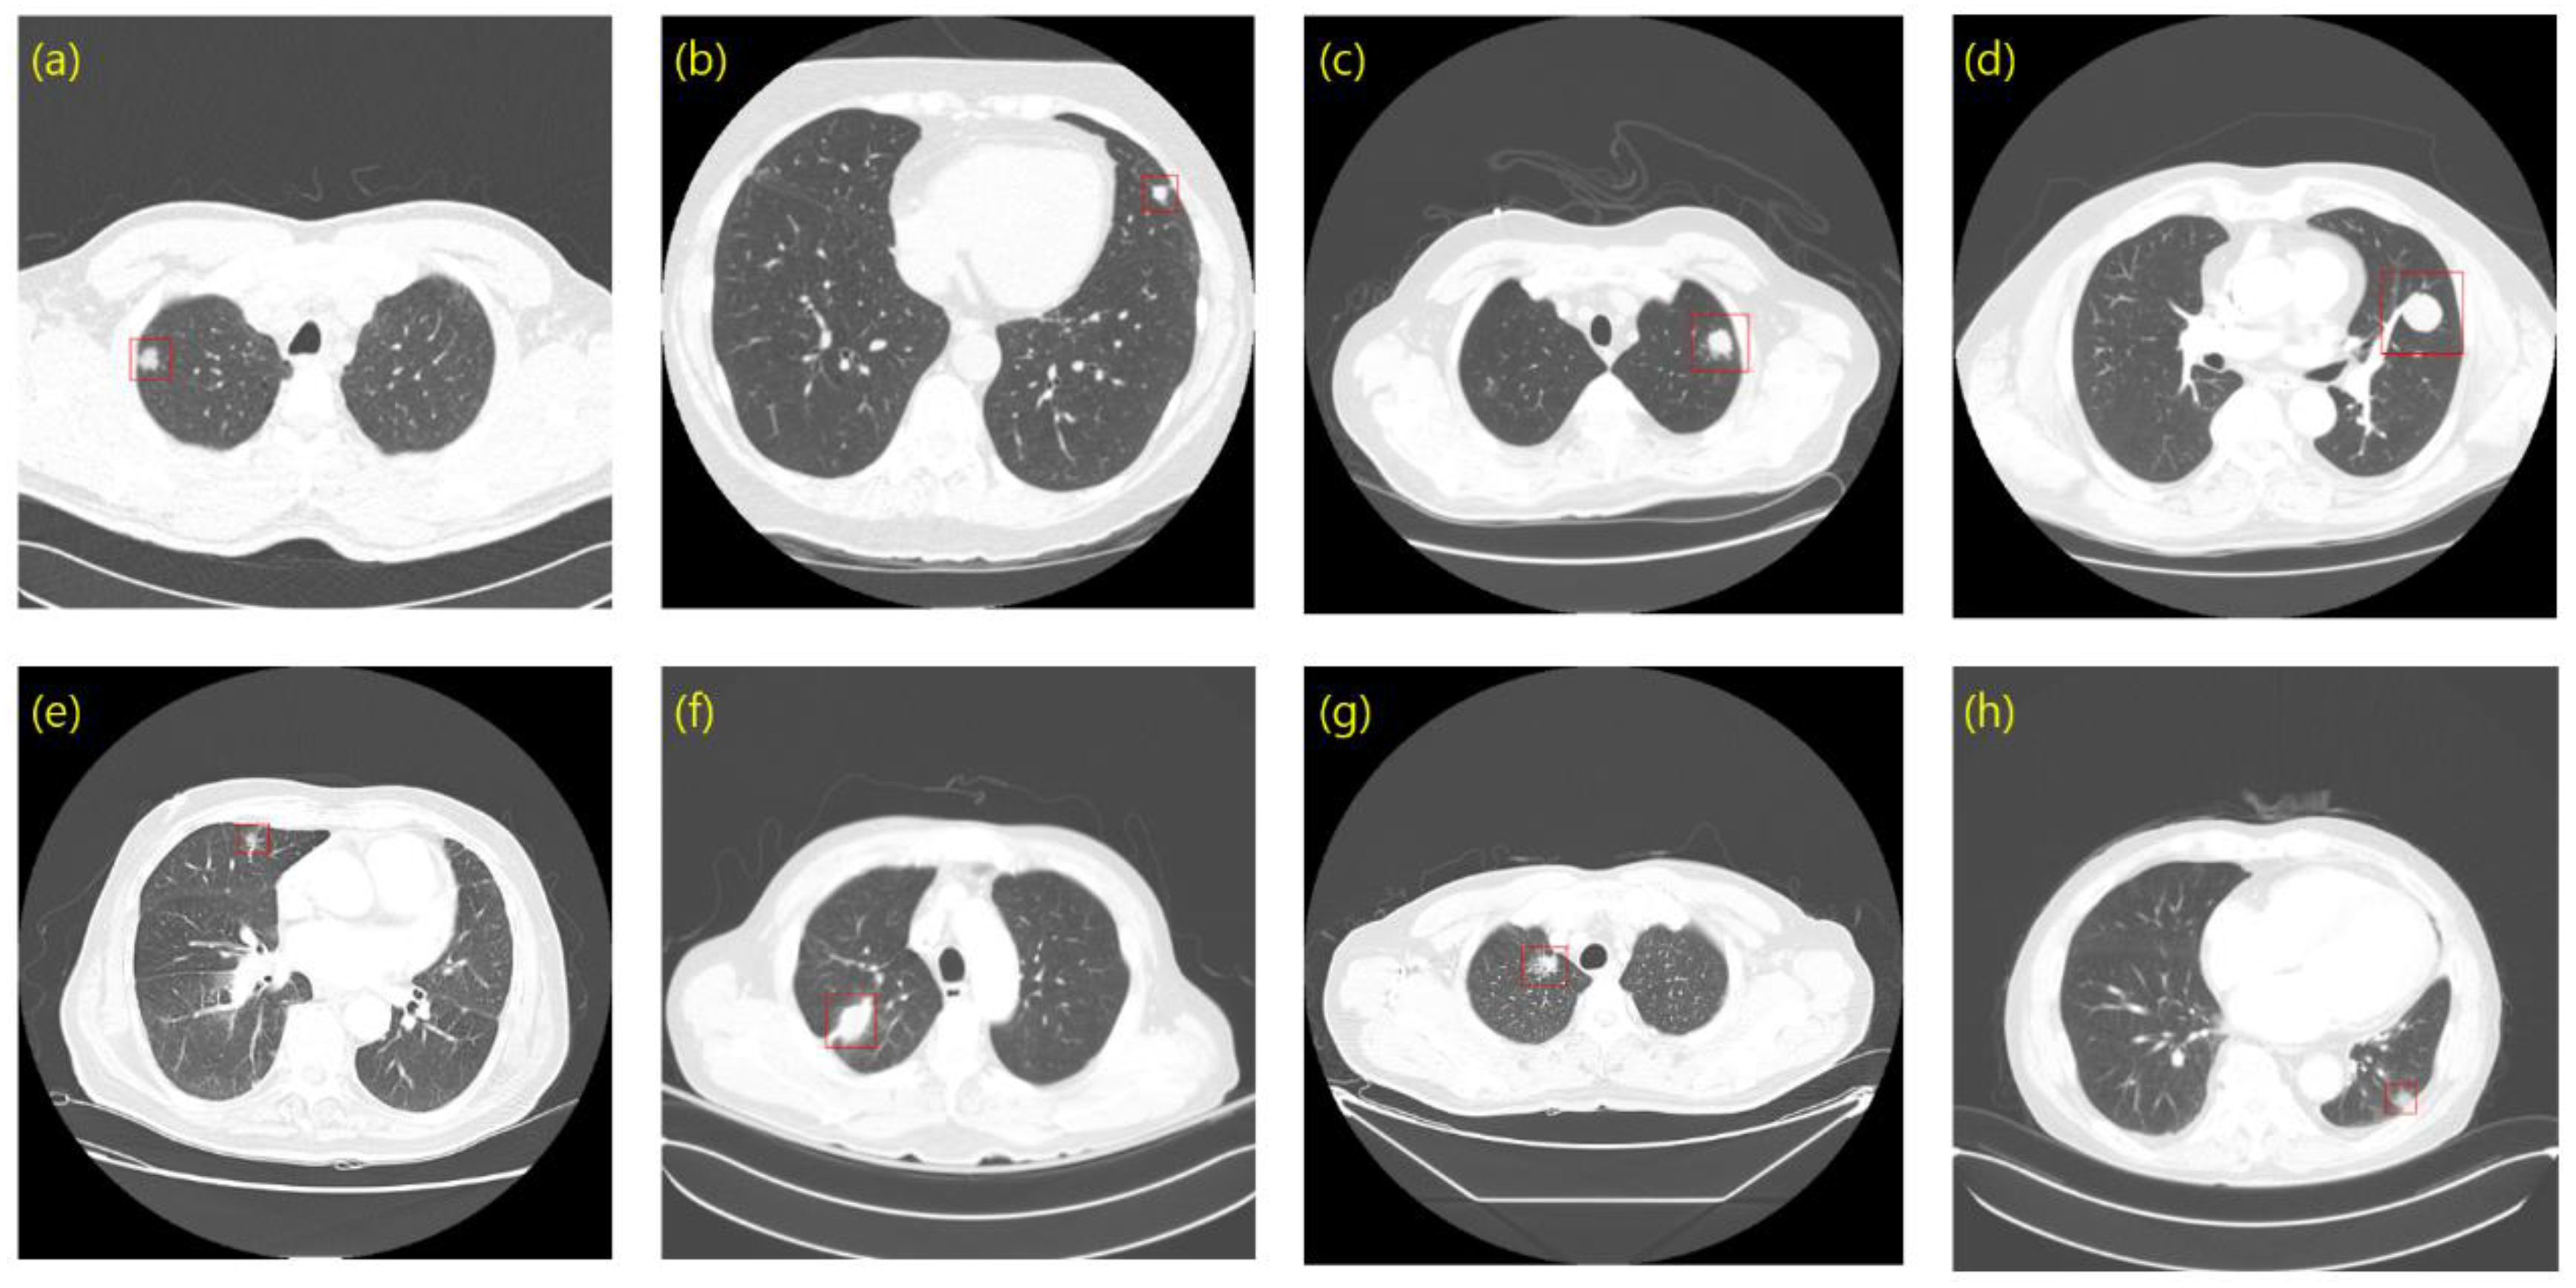

2.1.2. Private Dataset

2.1.3. Annotation